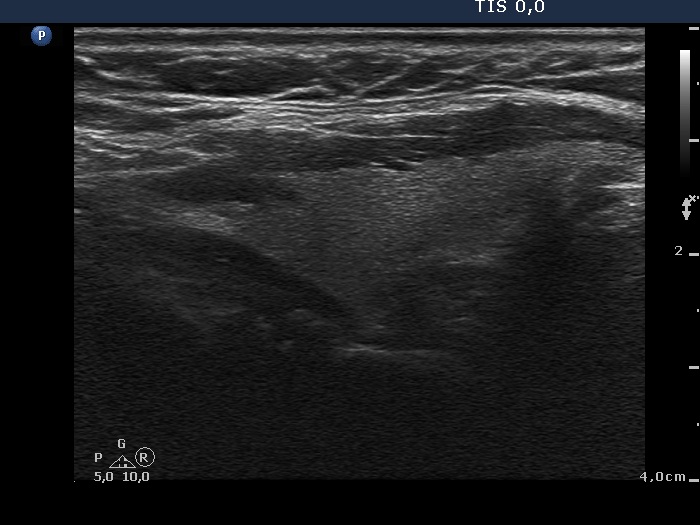

The borders of the nodule - case conp 051 (ultrasonographic picture 6)

Left lobe, longitudinal scan.